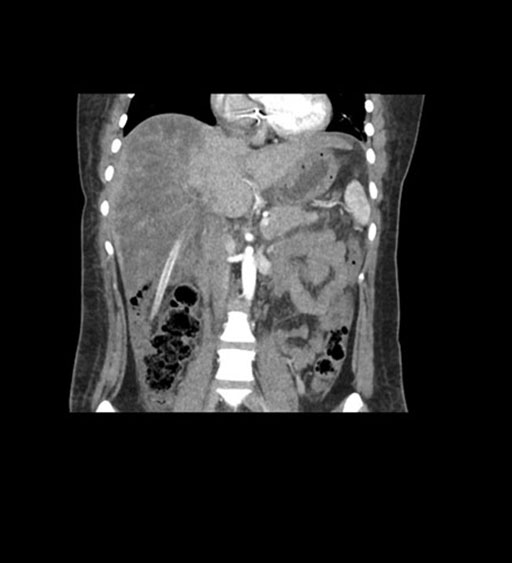

Coronal Arterial